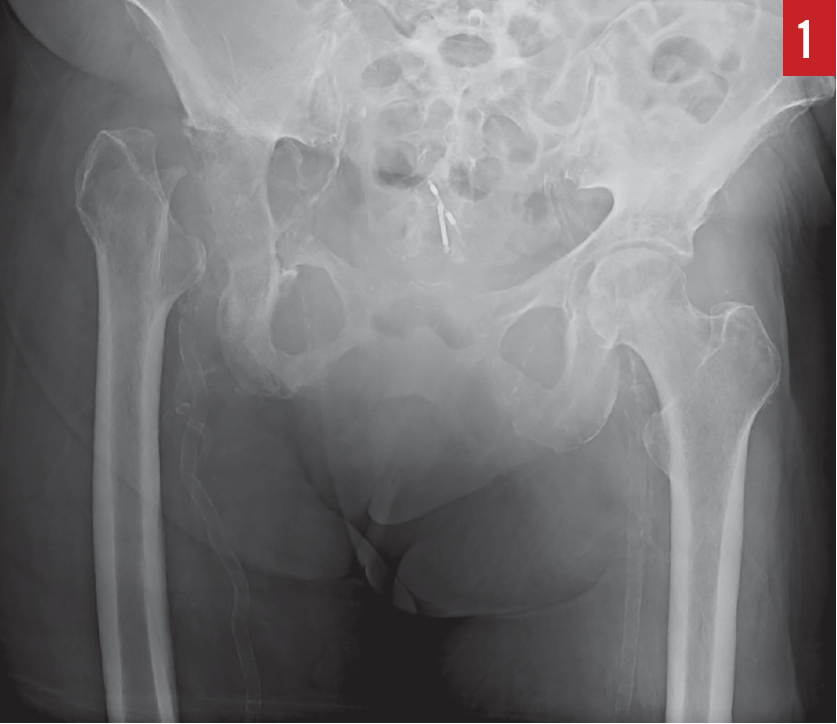

Diagnostic tests. Results of a complete blood cell count included an elevated white blood cell (WBC) count of 15,800/µL with a predominance of neutrophils, and a hemoglobin level of 10.3 g/dL. Urinalysis was positive (3+) for leukocyte esterase, negative for nitrite, and positive (4+) for bacteria, with greater than 182 WBCs per high-power field. Subsequent urine culture results were negative for pathogens. An anteroposterior radiograph of the pelvis (Figure 1) and a magnetic resonance imaging scan of the pelvis (Figure 2) showed the absence of the right femoral head and acetabulum.

Based on these findings, the patient received a diagnosis of osteomyelitis.